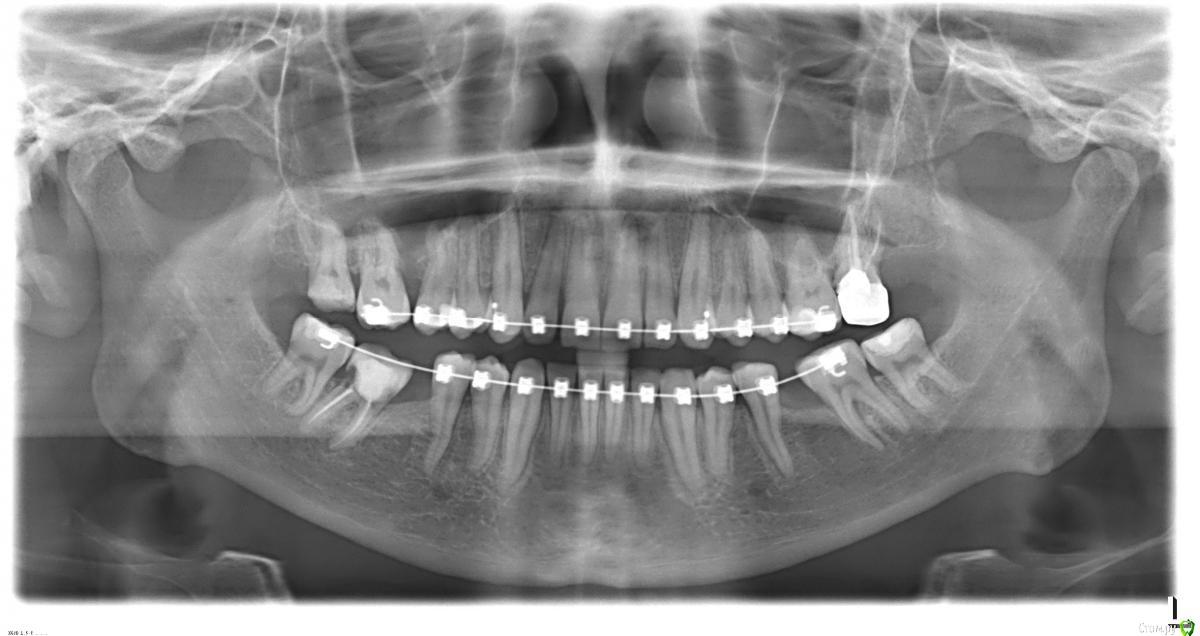

IvS Опубликовано 3 марта, 2019 Поделиться Опубликовано 3 марта, 2019 (изменено) Здравствуйте, уважаемые доктора! В январе 2018 года мне были установлены брекеты для исправления скученности зубов, выравнивания центральной линии и увеличения места для будущей установки имплантов на месте удаленных 10 лет назад шестерок. Прошел год и ортодонт направил на консультацию к имплантологу. Врач изучил КТ и сказал, что поставить импланты можно только после удаления нижних зубов мудрости. Нижняя правая семерка так же будет удаляться, т.к. там трещина корня. После консультации нахожусь в замешательстве, так как к своим 31 годам уже потерял столько жевательных зубов. Действительно ли стоит удалять нижние семерки или есть другие варианты? Так же отсутствует 6 зуб на верхней челюсти, на его место уже почти встал 7, а на место седьмого двигается 8. Требуется ли удаление верхней восьмерки в моем случае? А еще смущает то, что имплантолог сказал, что не требуется подсадка кости на нижней челюсти, хотя зубы были удалены давно и десна визуально истончилась. Планируем устанавливать импланты Ankylos. ОПТГ во вложении, так же сейчас попробую загрузить КТ. Ссылка на КТ https://drive.google.com/open?id=16ia51DRlno_Nztn89iQ_d-6nZ_f6HAcP Буду очень признателен за Ваши ответы! Изменено 3 марта, 2019 пользователем IvS Ссылка на комментарий

колесников Опубликовано 3 марта, 2019 Поделиться Опубликовано 3 марта, 2019 38 удаление,37 дистализация,36 имплантация. 47 удаление . 48 пожалуй лучше удалить иначе будет сложно протезировать на имплантах. 46,47 имплантация. 1 Ссылка на комментарий

колесников Опубликовано 4 марта, 2019 Поделиться Опубликовано 4 марта, 2019 27ой в перспективе удалится,свои ресурсы он исчерпал. 17,16 окклюзионные вкладки. По поводу пластики на нч. Решать будет ваш лечащий врач после удавления и дистализация 7рок по клкт. Очевидно что в области 6рок узкий гребень,тактика от врача зависит. Я не делаю в подобных случаях костных пластик. 1 Ссылка на комментарий